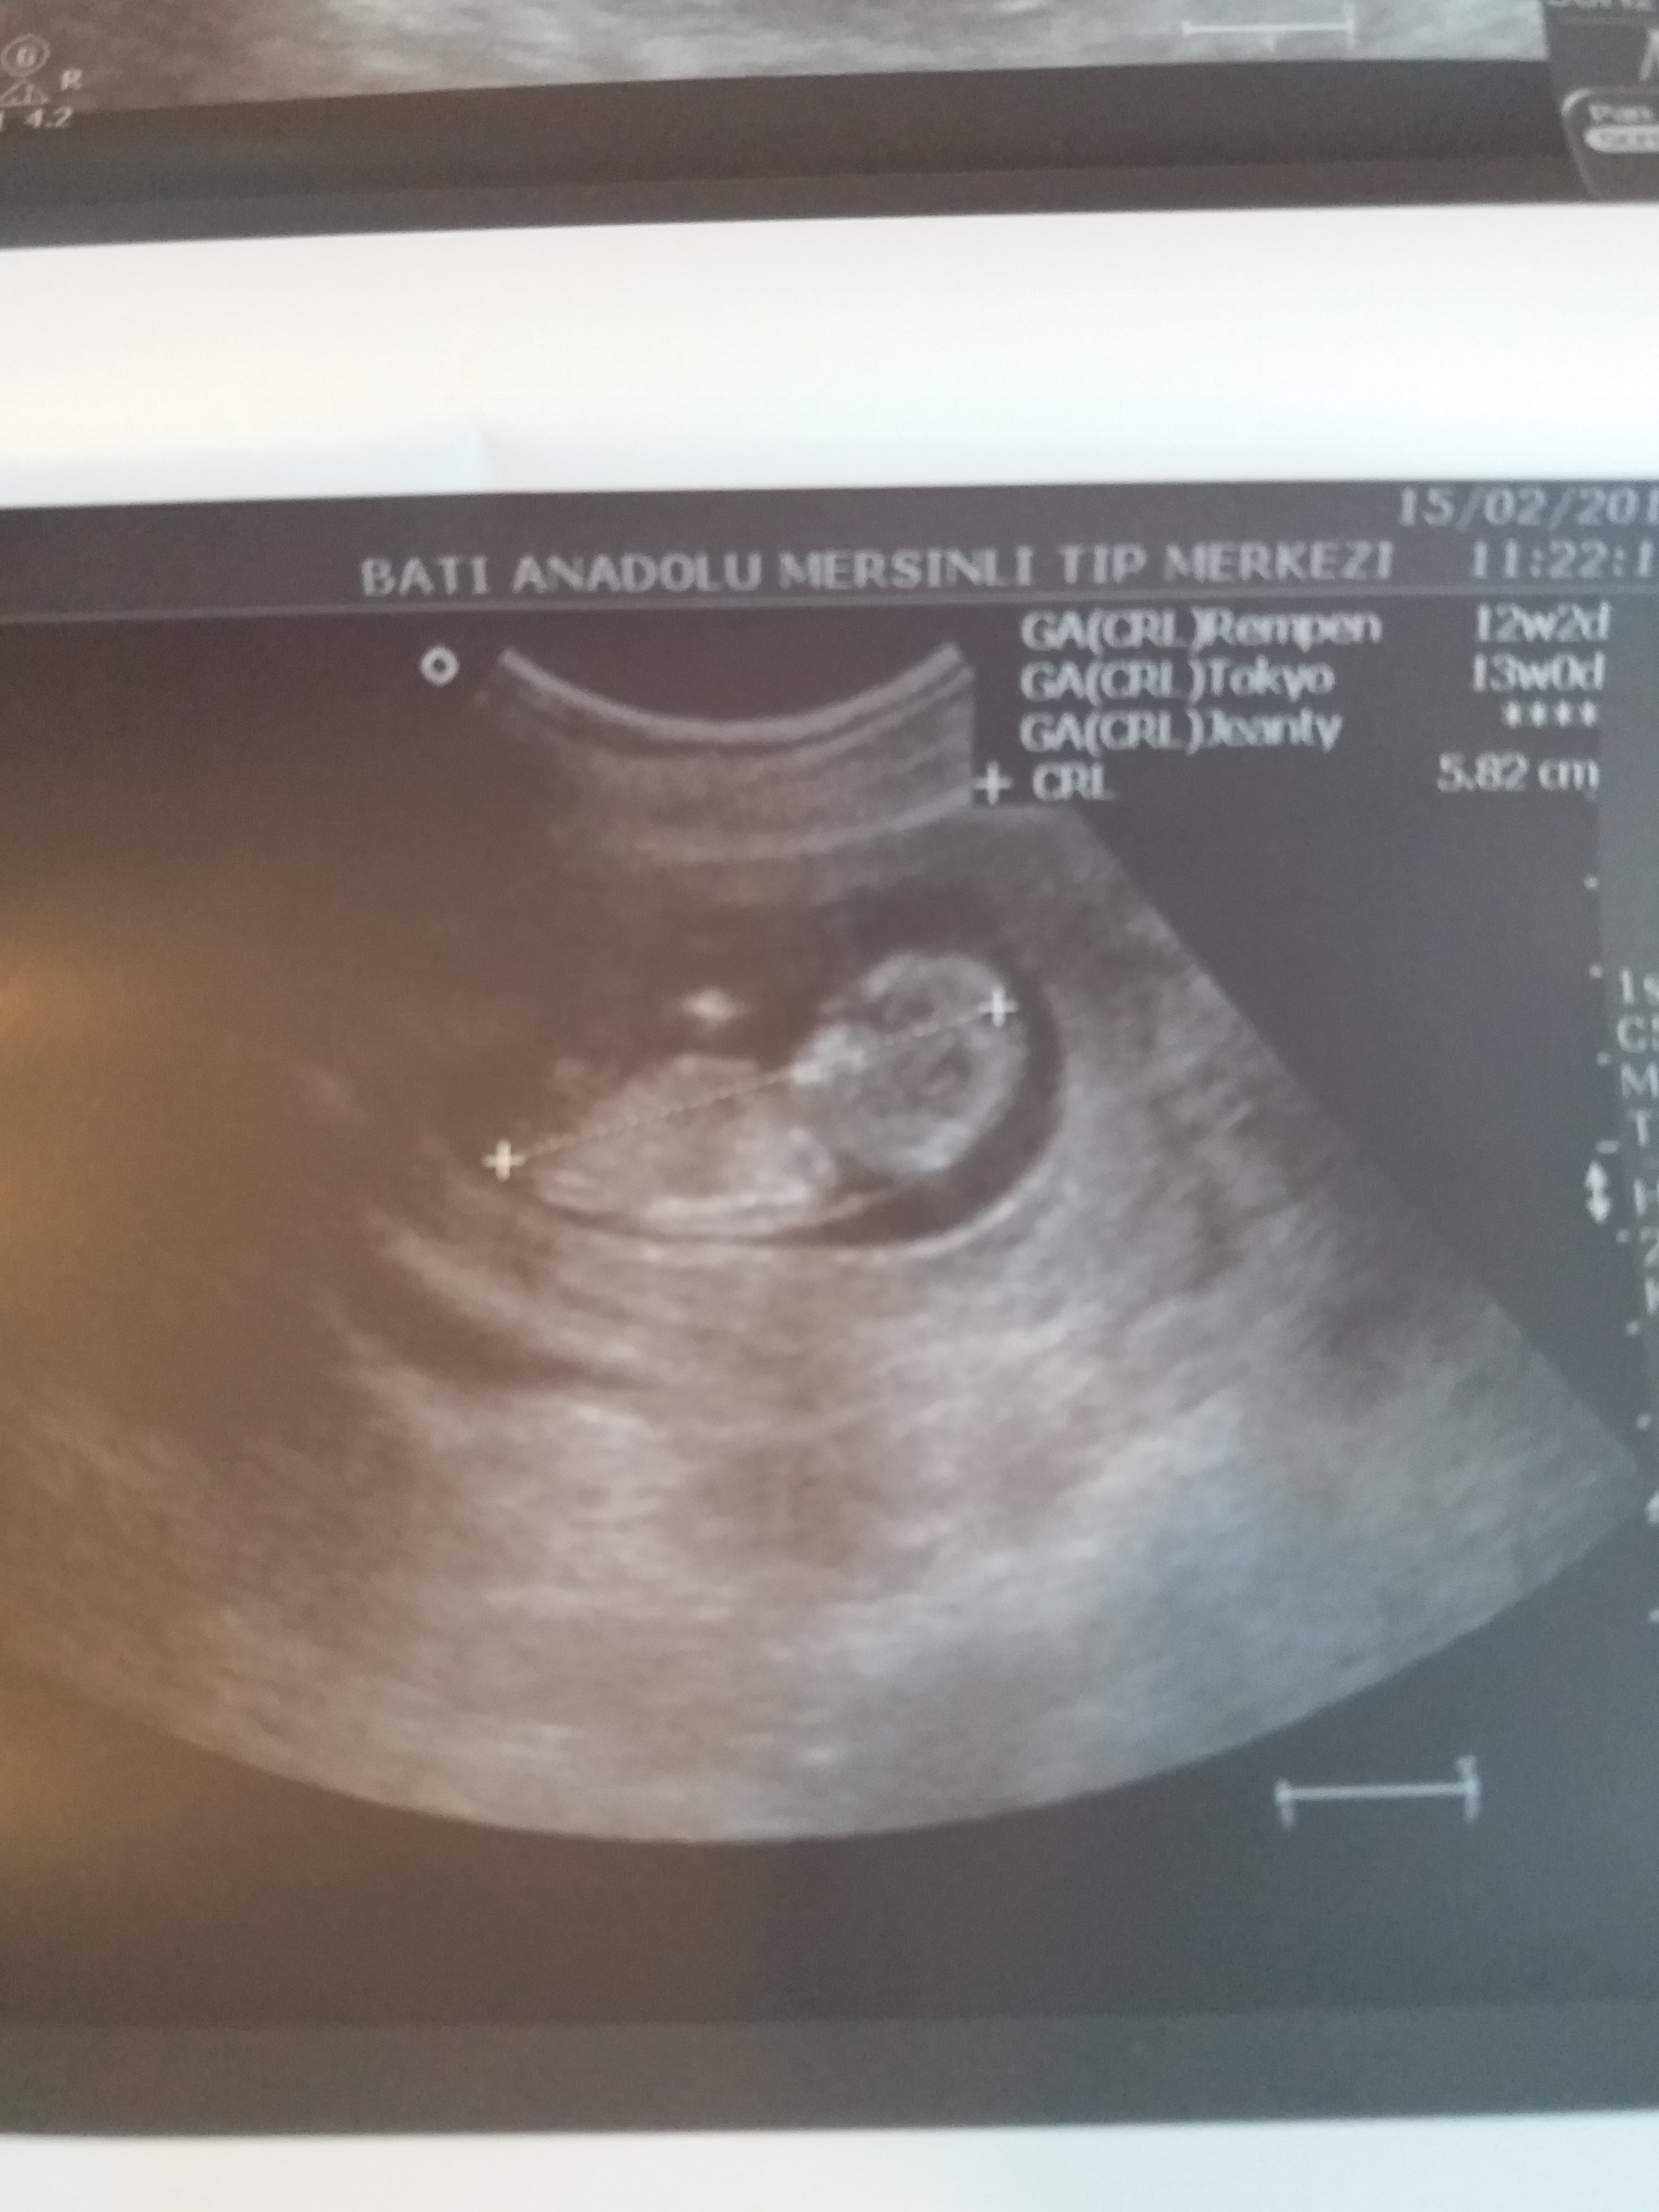

Banada yorum yapabilirmisiniz

Merhaba, emin olmamakla birlikte bebeğinizin cinsiyetinin erkek olduğunu düşünüyorum. Bebeğinizin cinsiyetini net olarak 16-17 - 20 haftalarda izlenebilir.